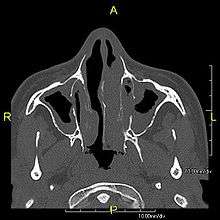

The main consequence of impaired ciliary function is reduced or absent mucus clearance from the lungs, and susceptibility to chronic recurrent respiratory infections, including sinusitis, bronchitis, pneumonia, and otitis media. Progressive damage to the respiratory system is common, including progressive bronchiectasis beginning in early childhood, and sinus disease (sometimes becoming severe in adults). However, diagnosis is often missed early in life despite the characteristic signs and symptoms.[1] In males, immotility of sperm can lead to infertility, although conception remains possible through the use of in vitro fertilization and, as well as this, there have been reported cases where sperm were able to move.[2] Trials have also shown that there is a marked reduction in fertility in female sufferers of Kartagener's Syndrome due to dysfunction of the oviductal cilia.[3]

Many affected individuals experience hearing loss and show symptoms of glue ear which demonstrate variable responsiveness to the insertion of myringotomy tubes or grommets. Some patients have a poor sense of smell, which is believed to accompany high mucus production in the sinuses (although others report normal - or even acute - sensitivity to smell and taste). Clinical progression of the disease is variable with lung transplantation required in severe cases. Susceptibility to infections can be drastically reduced by an early diagnosis. Treatment with various chest physiotherapy techniques has been observed to reduce the incidence of lung infection and to slow the progression of bronchiectasis dramatically. Aggressive treatment of sinus disease beginning at an early age is believed to slow long-term sinus damage (although this has not yet been adequately documented). Aggressive measures to enhance clearance of mucus, prevent respiratory infections, and treat bacterial superinfections have been observed to slow lung-disease progression. Although the true incidence of the disease is unknown, it is estimated to be 1 in 32,000,[4] although the actual incidence may be as high as 1 in 15,000.